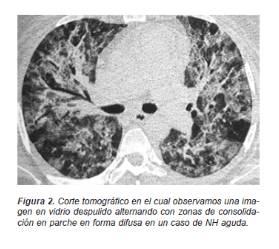

En las formas agudas de la NH se presenta un aumento de la densidad parenquimatosa con una atenuación en vidrio despulido en parches o difusa del espacio aéreo (Figura 2).